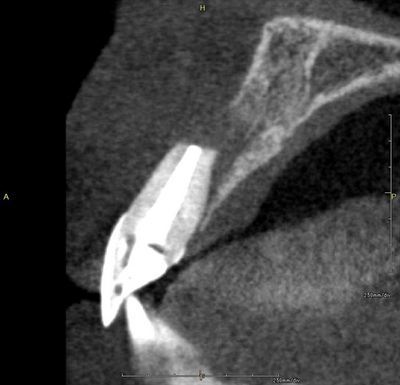

過去に歯根端切除手術がなされており、歯根が短くなっています。

歯根の先端に球状の病変が存在しており、歯根自体に亀裂が入っています。

唇側骨がほぼ全て欠損しています。

やはり歯根は短く、明確な亀裂も入っています。

抜歯した右上中切歯です。

亀裂が口蓋側にも入っています。

歯根端切除手術は当然のことながら歯根が短くなるため、私は肯定的ではありません。